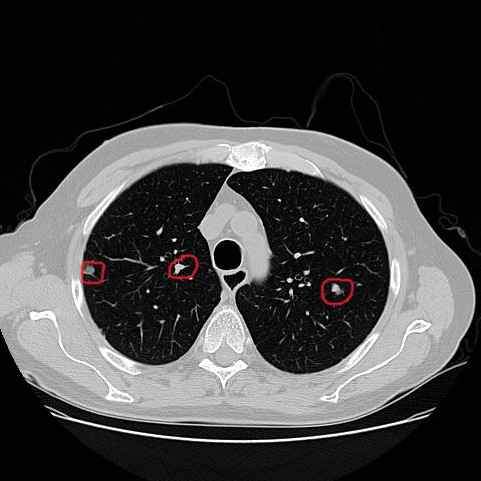

请问中间这个是肺结节吗

毕设自己训练的模型,用的LUNA16数据集,最后识别为肺结节的有三处,数据集标注的只有两侧为肺结节,很好奇中间这块是什么,肺淋巴结还是其它?恳请各位老师或同学解答。如图: 发自小木虫Android客户端 |